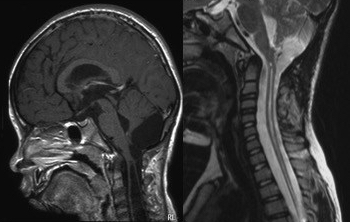

ce néologisme a été formé pour désigner les cas de syringomyélie associés à une position basse des tonsilles cérébelleuses mais sans engagement véritable. Il existe en fait une fibrose méningée qui bloque la circulation du liquide cérébrospinal.

avant tout il faut écarter une hydrocéphalie évolutive, sinon, il s’agit d’une malformation de Chiari qui nécessite une exploration endo-durale avec dissection arachnoïdienne et remise en communication du quatrième ventricule avec les citernes ; la mise en place d’un stent semble judicieuse.